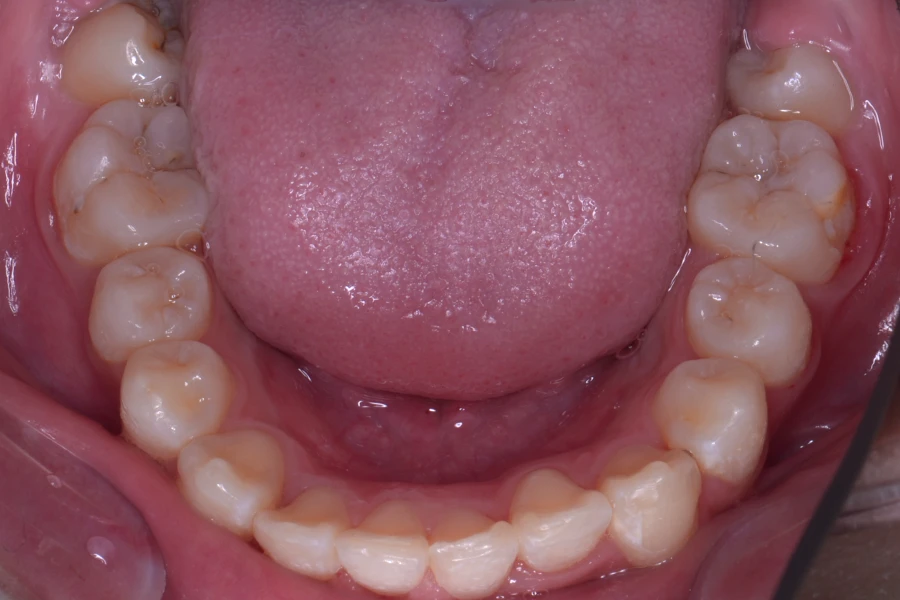

• 治療前

• 治療後

主訴 八重歯を治したい

治療内容 上下顎ラビアル矯正(表側矯正)

治療に伴うリスク 後戻り